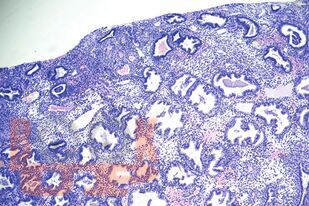

Учебное пособие содержит материалы, касающиеся терминологии, распространенности, современных классификационных принципов, морфологии и терапии эндометриальных полипов. Пособие составлено в соответствии с рабочими программами дисциплин «Патологическая анатомия», «Акушерство и гинекология» и разработано с учетом положения «Требования к структуре, содержанию и порядку оформления учебных изданий» СМК П 13-2019, утвержденного приказом ректора ФГБОУ ВО ЮУГМУ Минздрава России от 30.08.2019 № 215, введено в действие с 02.09.2019.